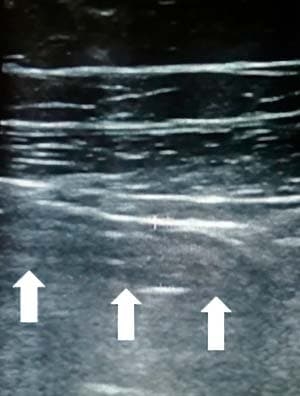

Обнаружение увеличенных лимфоузлов (более 5 мм в поперечнике) по ходу корня брыжейки тонкой кишки является вторичным признаком воспаления в илеоцекальной области при остром аппендиците (см. рис. 14). Этот признак неспецифичен для острого аппендицита, поскольку лимфаденопатия в брюшной полости может быть как при аппендиците, так и без него, являясь частой реакцией на воспалительные заболевания толстого и тонкого кишечника, а также может отмечаться при первичном мезадените. Увеличенные лимфоузлы имеют вид гипоэхогенных овальных структур, несжимаемых при компрессии.

Рисунок 14. Увеличенный лимфоузел.